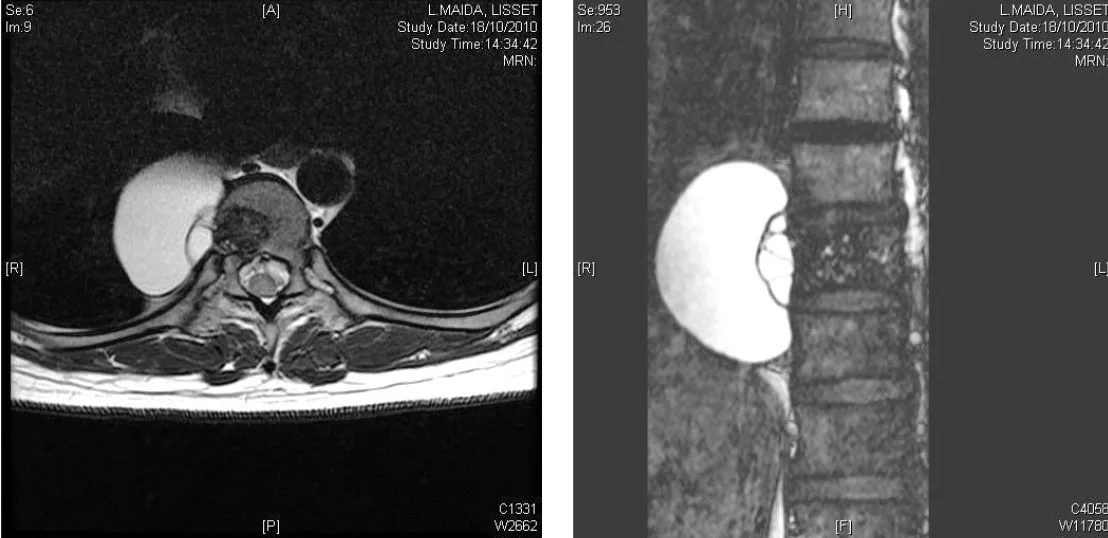

Quiste hidatídico

Los parásitos también pueden causar espondilodiscitis, siendo el quiste hidatídico el ejemplo más relevante. Esta parasitosis, causada por el Echinococcus granulosus, puede afectar a la columna vertebral de forma primaria o como parte de una enfermedad diseminada. El diagnóstico suele ser complejo y el tratamiento requiere tanto medidas farmacológicas como quirúrgicas.

Resonancia magnética (RM)

Constituye la prueba de imagen de elección para el diagnóstico y seguimiento de la espondilodiscitis. La RM presenta una sensibilidad y especificidad superior al 90%, permitiendo una visualización óptima del disco, los cuerpos vertebrales, los abscesos epidurales y la afectación de partes blandas paravertebrales.

- Descompresión: liberar la médula espinal y las raíces nerviosas de cualquier compresión causada por abscesos, fragmentos óseos o deformidad.

- Estabilización: restaurar la estabilidad de la columna mediante instrumentación con tornillos y barras, y en ocasiones con injertos óseos o cajas intersomáticas.